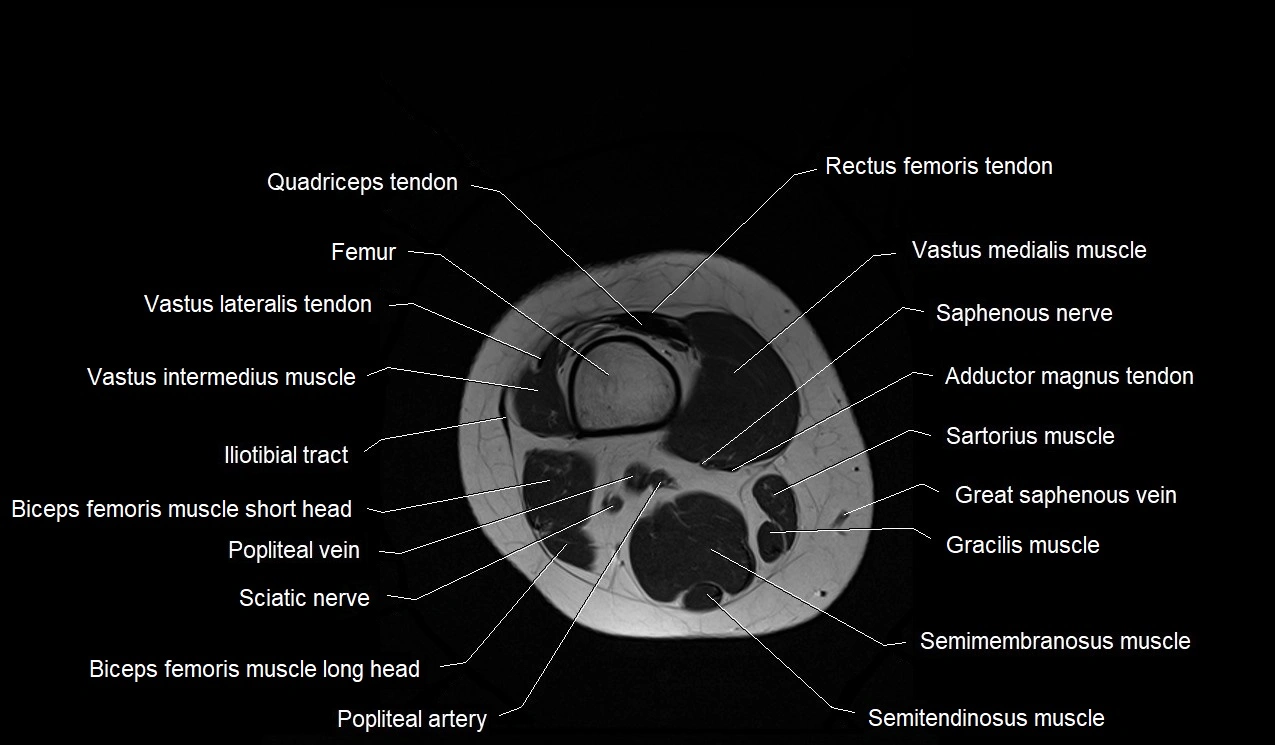

- Biceps femoris muscle (Long head)

- Biceps femoris muscle (Short head)

- Distal adductor magnus tendon

- Distal quadriceps femoris tendon

- Distal rectus femoris tendon

- Distal vastus intermedius tendon

- Distal vastus lateralis tendon

- Distal vastus medialis tendon

- Gracilis muscle

- Iliotibial tract

- Popliteal artery

- Popliteal vein

- Saphenous nerve

- Sartorius muscle

- Semimembranosus muscle

- Semitendinosus muscle

- Tibial nerve